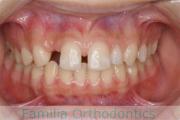

No.23V-308

- 主な症状:

- 欠損歯

- その他の症状:

- 空隙歯列

- 年齢:

- 17歳

- 性別:

- 女性

- 抜歯部位

- 上:

- 22欠

- 主な使用装置:

- Invisalign

- 治療にかかった費用:

- 88万円

永久歯がない為、隙間を埋めたいとのことで来院されました。検査診断を行ったところ、上の側切歯が左右とも欠損しているものの、矯正で歯を動かして隙間をすめて埋めるのは無理があるという判断になり、左上の乳歯は保存したまま、スペースは全て右上に集めました。マウスピース型矯正装置のひとつ、インビザライン/Invisalign®(薬機法および医薬品副作用被害救済制度の対象外)を使用しています。

歯の移動後に、右上にインプラントを埋め込む予定ですが、まだ若年のため、人工歯を接着剤とワイヤーで固定しています。